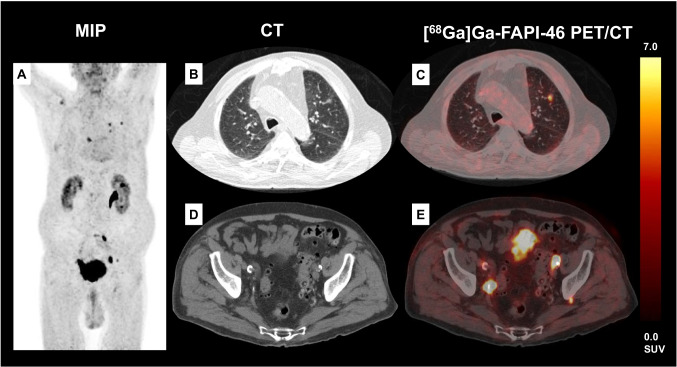

Fig. 1.

Exemplary patient (A: maximum intensity projection (MIP)) with [68Ga]Ga-FAPI-46-positive lung metastases of UC in the left upper lobe (B, C) that were confirmed by histopathology (for histological correlation see also Fig. 2). This patient also presented with a small configuration behind the left acetabular bone (D) which could have been missed as lymph node metastases without the increased [68Ga]Ga-FAPI-46 expression (E)